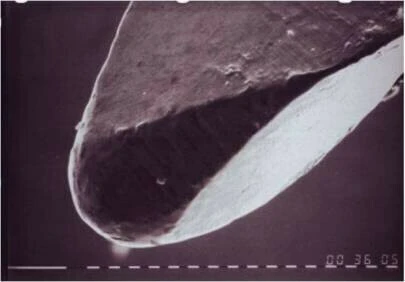

Những thí nghiệm gần đây về hiệu quả của sự thay đổi hình dạng đầu trâm đến việc sửa soạn ống tủy cho thấy:

Những trâm nội nha với đầu trâm không có tác dụng cắt (bằng cách giảm độ nhọn của đầu trâm hay giảm sự góc cạnh và liên kết các mặt phẳng hướng dẫn lại với nhau) giúp giảm sự di chuyển ống tủy và giúp loại bỏ mô ngà nhiều hơn ở thành trong đoạn cong (phần cong lõm) so với các trâm nội nha với đầu trâm truyền thống.

Có bằng chứng rõ ràng cho thấy: dụng cụ với đầu trâm được thay đổi giúp duy trì hình dạng cong của ống tủy ban đầu, không liên quan đến vật liệu làm nó là trâm bằng thép không rỉ hay dụng cụ nickel-titanium tay hay dụng cụ nickel-titanium quay máy. Tuy nhiên, thậm chí dụng cụ bằng thép không rỉ với đầu trâm không có tác dụng cắt thì vẫn không mang đến kết quả tốt nhất với những ống tủy cong nhiều.